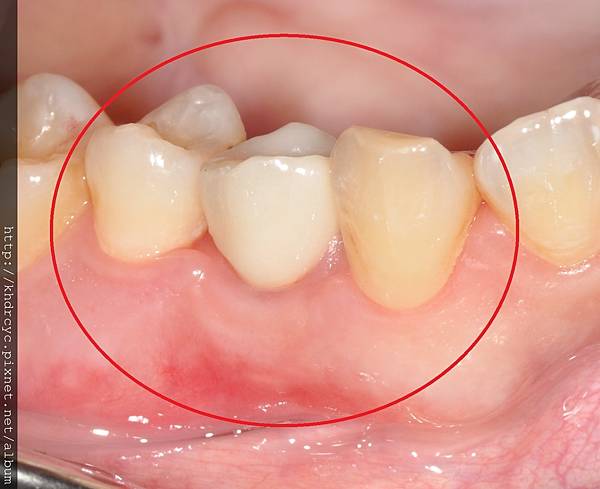

楠梓H小姐牙齒爛掉已久有相同問題

一直不敢看牙醫 鼓起勇氣請欣美牙醫幫忙

欣美牙醫幫忙在植牙手術中同時補骨

楠梓H小姐非常有信心的預約下一顆植牙

了解植牙手術中同時補骨

恢復牙肉與牙齒的外觀與厚度

完全感覺不出植牙跟一般牙齒的差別